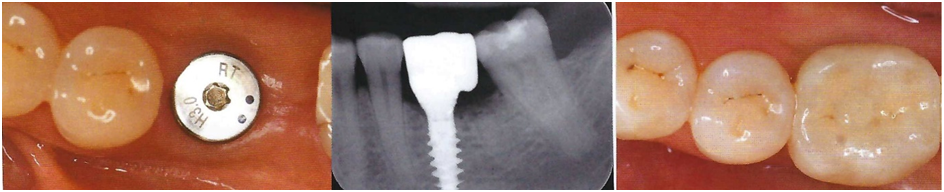

At Kick Ass Dental, we refer all dental implant procedures to a trusted local specialist. We believe that partnering with an expert in implantology ensures the highest standard of care and leads to more successful, long-lasting outcomes for our patients.